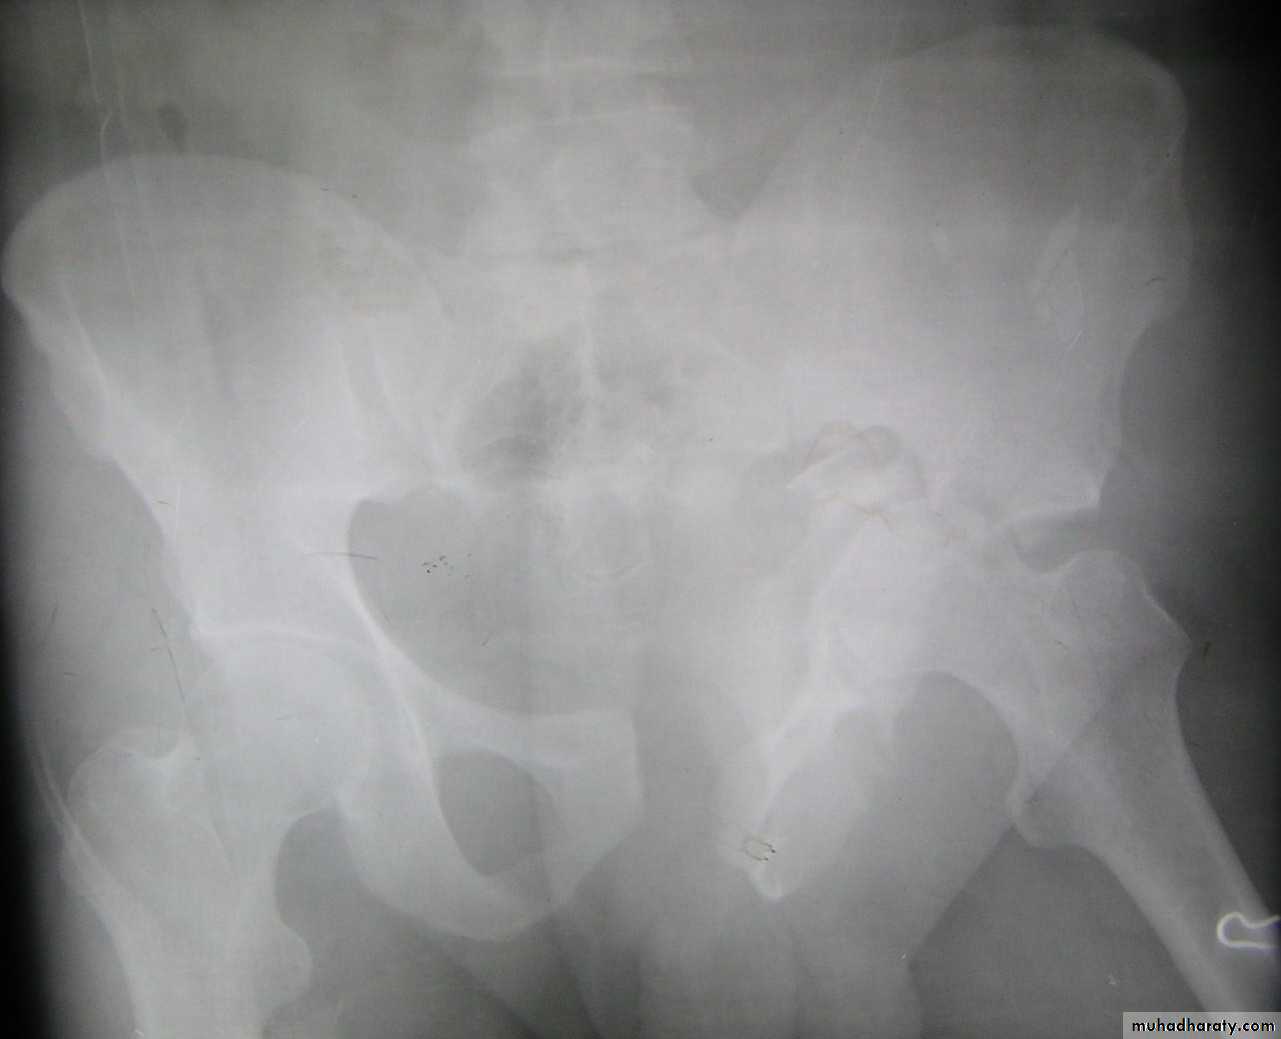

HIP DISLOCATION

Traumatic Dislocations of the hip.

Posterior.

Anterior.

Central.

Posterior dislocation:

The golden role is to x ray the pelvis in every case of sever injure

and with femoral fracture to include both the hip and knee.

Radiological examinations

X-R AP view we can see the dislocation with or without associated fracture posterior wall of the acetabulum,

or fracture head of the femur,

And neck of femur.